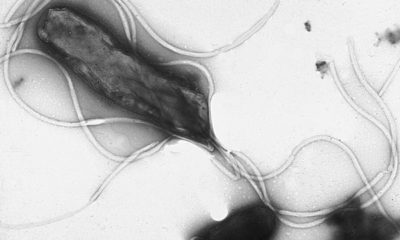

Helicobacter pylori является основным патогенным микроорганизмом желудка, вызывающим гастрит, язвенную болезнь, аденокарциному желудка и низкодифференцированную лимфому желудка....